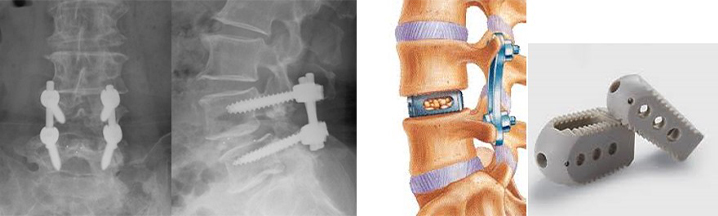

5. 側方椎体間固定術(LLIF)

側方椎体間固定術(LLIF)は腰椎に対して体の側面から椎間ケージといわれるスペーサーを椎間板腔に入れる方法です。側臥位(横向き)で手術を行います。筋肉などの組織を分けて手術するので組織のダメージが比較的少ない低侵襲な方法です。椎間ケージも体の後方より入れる方法(PLIF)に比べて大きなサイズのものが挿入可能で、椎間矯正力や骨癒合率の向上が期待できます。ただ手術の際に骨盤により進入経路が制限されることがあり、手術の適応にならないことがあります。

手術は横向きになり体の側面から手術をします。

組織を分けて(左図)、cageを椎間板内に挿入しているところです。

椎体のすべり(ずれ)が矯正され神経の圧迫が取れています。